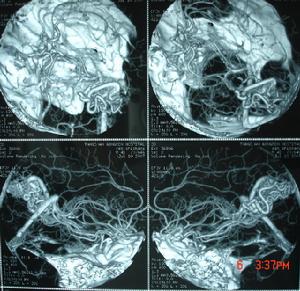

脑动静脉畸形有以下典型表现:①显示畸形血管。这是特征表现,呈一团管径相仿相互纠缠的迂曲扩张血管。畸形血管团的范围可小如指甲,大如手掌,多见大脑半球皮质.②异常粗大的供养动脉和引流静脉伴局部循环加快。此为局部血流短路的表现。③血流分流现象:造影剂随血流经畸形血管的短路大量流入静脉,因此,血管畸形部分因血流量增加而显影十分清楚。④血肿的表现:血管破裂出血致脑内血肿,血肿的主要表现为局部占位征象,一股脑部动静脉畸形无血肿时,脑血管不出现占位征象,脑血管不移位。 医学百科网 | YxBaike.Com

5.脑血管造影:最可靠、最重要的诊断方法,动脉期可见血管团、供血动脉及早期显现的引流静脉。 医学百科网 | YxBaike.Com

4、脑血管造影是本病最可靠和主要的诊断方法,并能行血管内介入治疗。